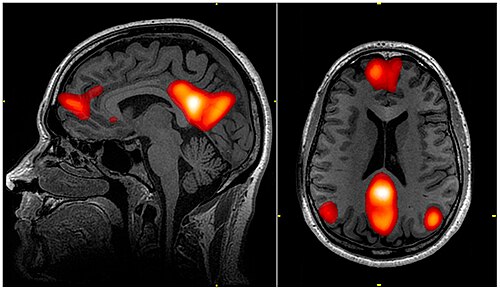

功能磁共振成像技术的应用揭示,在无外部任务要求时(即“静息态”),大脑存在大规模的、高度有组织的自发活动(Raichle, 2015)。这种活动并非噪声,而是一种与任务态相互拮抗的核心脑状态,为理解休息的主动功能提供了基础框架,即大脑在休息状态下并非完全停止工作,而是进入了一种被称为“ 默认神经网络 ” (Default Mode Networt, DMN) 的活跃状态。DMN在活跃状态下,个体会进行自我反思、记忆整合和未来规划等认知活动。